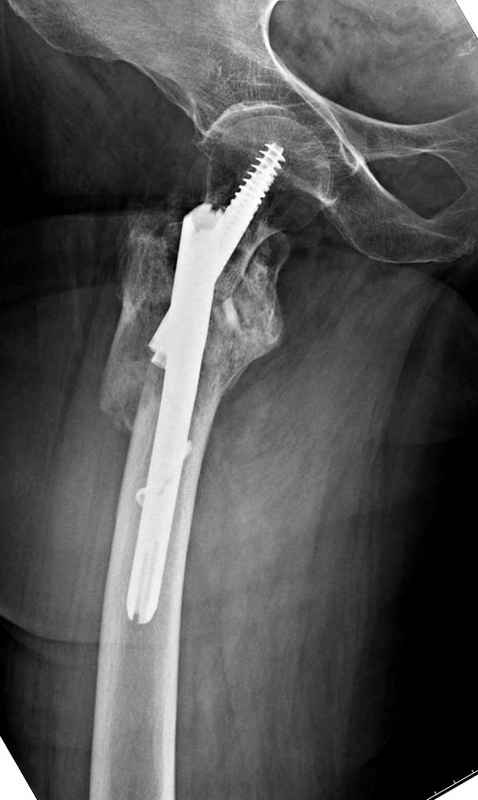

Из фиксаторов, мы бы применили цефаломедуллярные, потому что они "по закону моментов" из-за короткого рычага от центра головки к диафизу и по принципу "головка диафиз" механически лучше выдерживают нагрузки, чем пластины.

Здесь 83 года, травма в результате падения